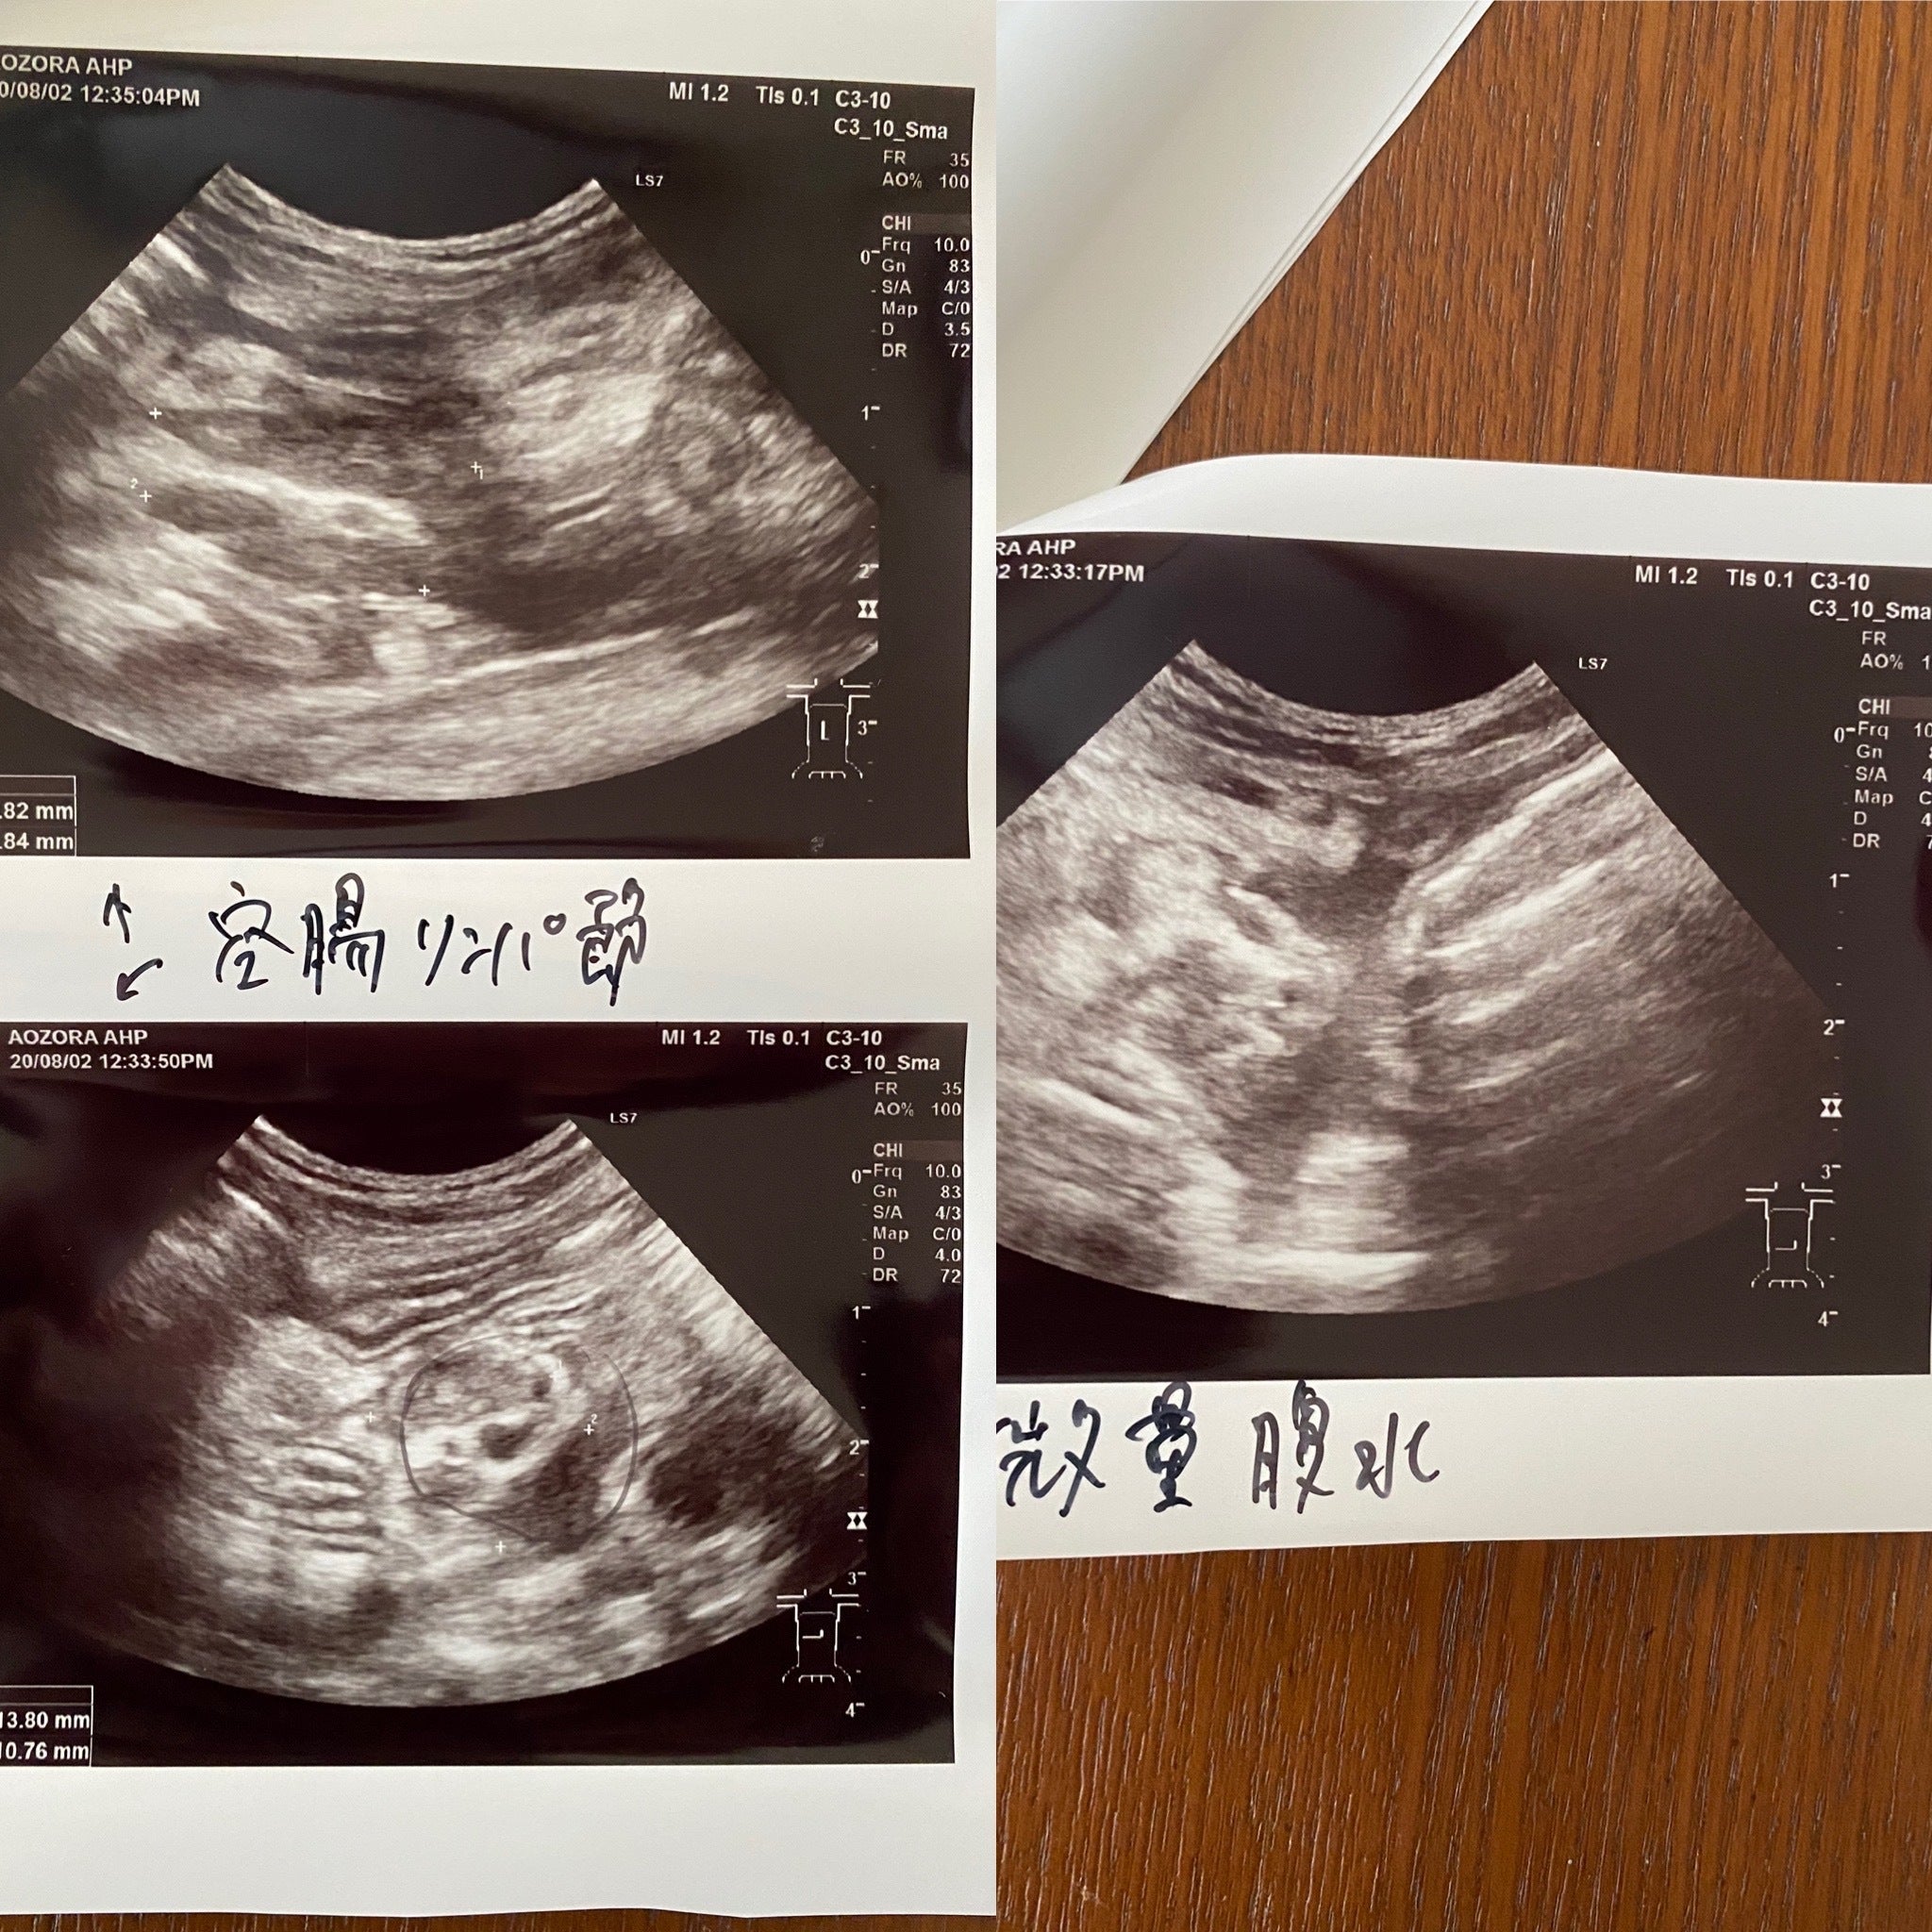

実は7年前に生後5ヶ月の子猫をこのFIPで亡くし非常に辛い思いをしました。そして今回のテオです。何とか治療を受けさせ治してあげたいと思い、色々と調べました。なんと偶然にも同じ市内にこのサプリメントの協力病院があるのを知りました。すぐに病院に電話し診察をして頂きました。結果はFIP混合型でした(FIPには3種類あり①ウエットタイプ②ドライタイプそして①②の混合型があります)。そして黄疸も出ており肝臓も良くないとの事でした。